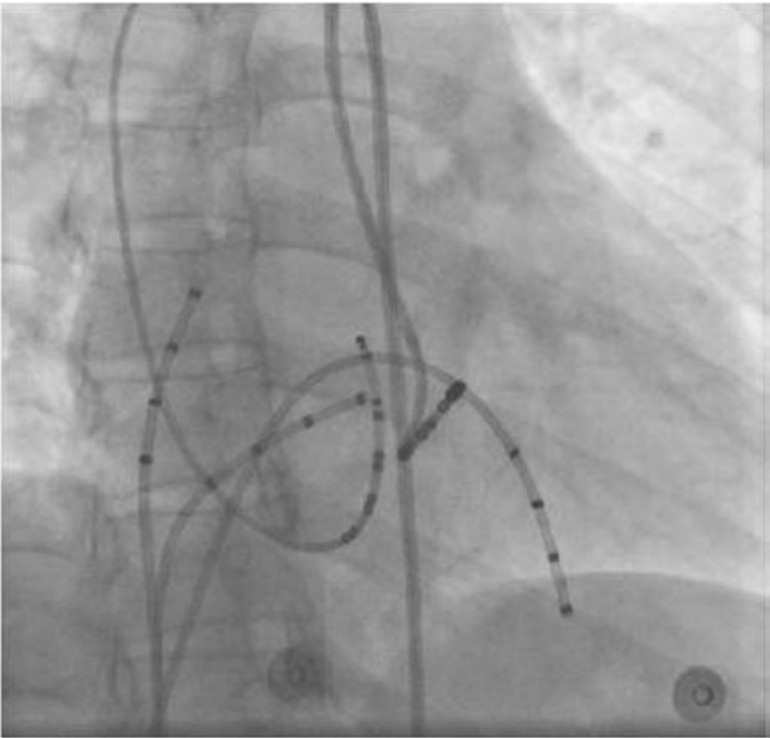

1.WPW综合征和隐匿性旁路的消融 在进行射频消融时,首先将多极电极导管分别置于高位右心房、希氏束区、右心室心尖部及冠状窦,进行电生理检查以明确诊断并标测旁路位置。冠状窦导管有助于左侧旁路的标测,并可作为心房、心室间分界线的解剖标志。经股动脉逆行途径在二尖瓣环心室侧标测消融,操作简单易行,是消融左侧旁路的常用途径。经动脉逆行途径在二尖瓣环心房侧标测消融适用于导管钩挂到瓣下困难,或虽可以钩挂在瓣下但不能成功消融等情况。也可利用房间隔穿刺技术,在二尖瓣环心房侧进行消融,是经动脉逆行途径必不可少的补充。其优点是导管容易到位并且易于消融成功,同时可避免损伤主动脉瓣,尤其适应于儿童患者;缺点是导管与瓣环贴靠不紧密,需要较高的功率,消融后复发率偏高,房间隔穿刺增加了操作时间,导管易穿破左心房导致心脏压塞。对左侧旁路患者,常用右前斜位(RAO)30°投照,该投照角度下,左心室长轴展开好,易指引消融导管钩挂到二尖瓣环下。左前斜位(LAO)45°是重要补充,在对导管走行有任何疑问时均应行LAO透视,这一透视角度有助于判断导管是贴靠于间隔还是游离壁,以避免损伤希氏束(图64-11)。

img1693

图64-11 隐匿性左侧旁路

右心室心尖部刺激S1s1=300ms,VA呈偏心性传导,逆传A波最早激动点在CS23,旁路靠近CS23。X线靶点见下图

img1694

RAO 30°

img1695

LAO 45°